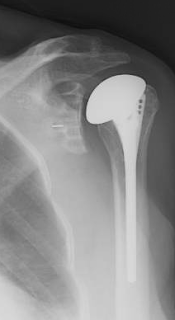

After a detailed discussion of the alternatives we decided to offer her a reverse total shoulder. The key step in the procedure was transecting the head from the shaft before attempting to dislocate the proximal humerus - it turns out that the displaced humeral head was tightly scarred to the brachial plexus. The post operative x-rays look like this. We will eagerly await her functional outcome.